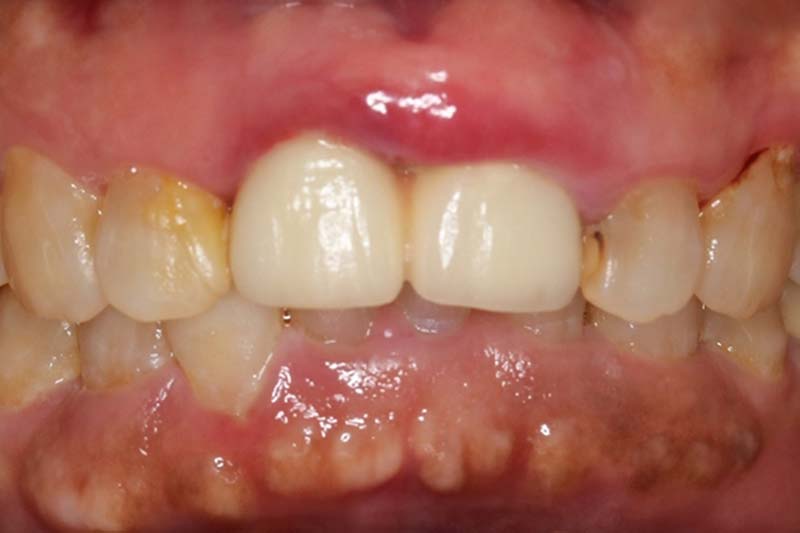

牙周治療前病患抱怨有膿在舊有的門牙植牙周邊,容易流血

經過牙周治療後,控制發炎,可見牙齦的狀況變得更健康了!

植牙臨時假牙試戴2週恢復狀況

臨時假牙微笑照